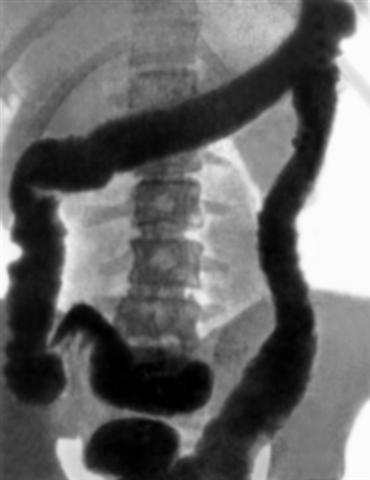

Рис. 1б). Обзорная рентгенограмма толстой кишки при тугом заполнении ее бариевой взвесью при быстро прогрессирующей форме язвенного неспецифического колита: пораженная толстая кишка имеет равномерный просвет, неровные контуры, гаустры ободочной кишки отсутствуют.